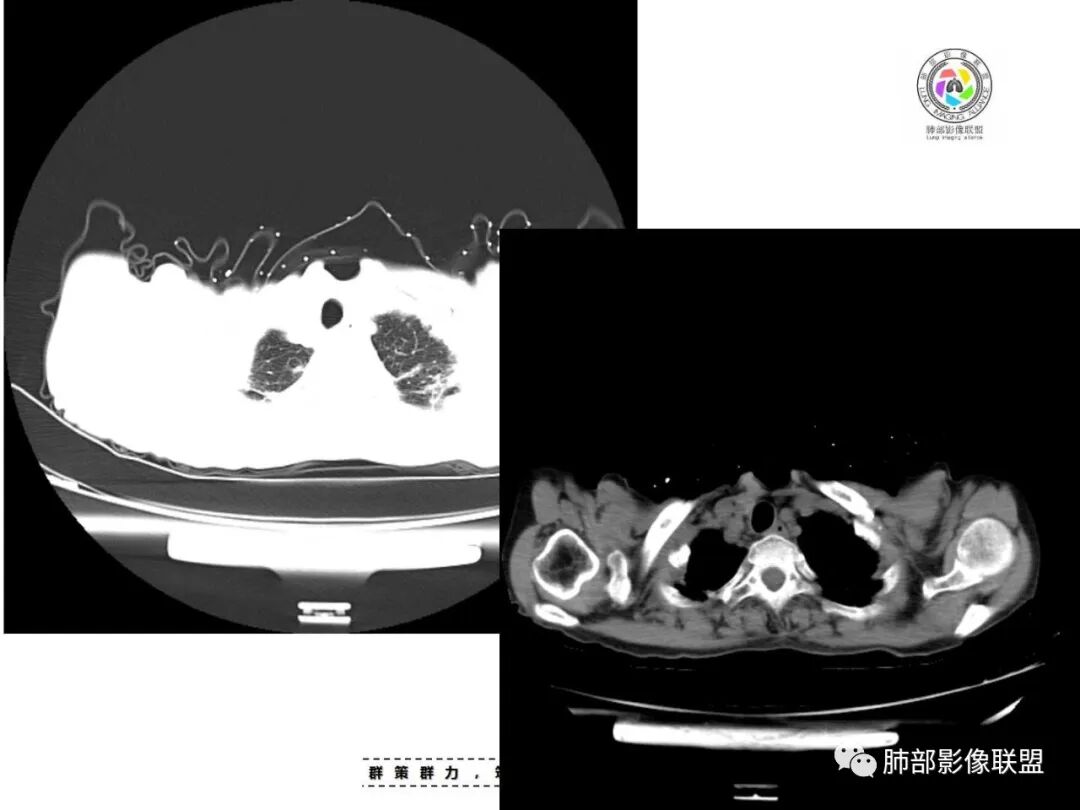

老年女性,67岁,咳嗽、咳痰半月余。双肺可闻及痰鸣音。

胸部CT:双肺上叶多发小结节,沿胸膜下、支气管血管束分布。右上肺斑片实变影、索条影及小叶间隔不均匀增厚,支气管枯枝征?纵隔淋巴结多发肿大,部分有钙化。综合考虑:结节病?尘肺?鉴别:腺癌并癌淋。

患者老年女性,亚急性起病,主要症状表现为咳嗽、咳痰半月余,查体:双现呼吸音粗,双肺可闻及痰鸣音。胸部CT:双上肺胸膜下可见多发小叶实变影,双上肺可见多发小叶中心性结节及小叶间隔增厚,右上肺后段可见亚段性实变影,内见多发空洞,前段可见GGO及树芽征,后段局部支气管闭塞,肺门淋巴结肿大并钙化。病灶整体:有气道、间质播散,一元论考虑肺结核合并支气管结核可能性大,建议好好查痰;这样病灶:明显实变+空洞+气道播散,若是结核,痰涂片找到抗酸杆菌应该没问题。建议支气管镜检查助诊,了解有无支气管结核及合并腺癌的可能。

1.双肺片状影、大小不等斑片影、结节影、树芽等,病灶密度偏高多钙化。

2.病灶上肺为主,胸膜下分布为主。双肺病灶明显不对称,右肺块状影较大。

3.纤维条索影广泛杂乱、牵拉,横向分布为主,这点给人也印象很深!

4.纵隔轻度右移。双肺门纵隔淋巴结增大钙化。

5.老年女性患者,咳嗽咳痰半月余